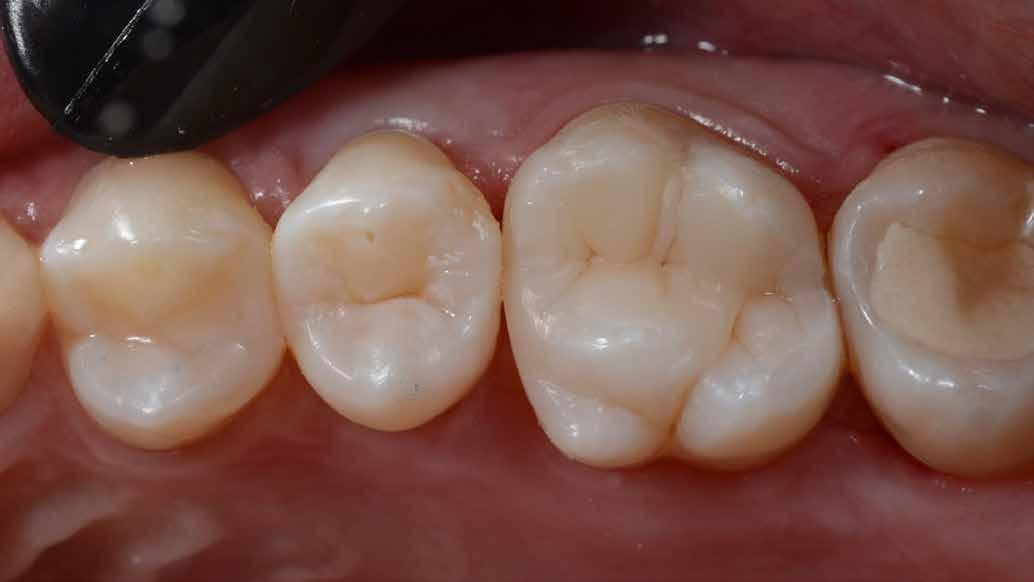

A restauráció polírozását korongok és szilikonpolírozók kombinációjával végezte, majd az okklúzió ellenőrzését követően a pácienst a rendelőből otthonába bocsátották. Megjegyzendő, hogy a finírozást követően az eredeti okkluzális anatómia csak minimális mértékben módosult (17. ábra).

A posterior fogak direkt kompozit restaurációja az egyik leggyakrabban végzett beavatkozás a fogászatban. Az elmúlt években kiemelt figyelem irányult az elérhető eredmények optimalizálására, különös tekintettel a II. osztályú kavitás dobozának (Class II box) kialakítására, és a polimerizációs zsugorodásból eredő feszültség kezelésére. A téma körüli széles körű szakmai diskurzus ellenére van egy olyan lépés, amely gyakran nem kapja meg a kellő figyelmet: a mechanikai formázás protokollja. A mechanikai formázás alatt a restauráció kontúrjának kialakítását, a felesleges kompozit eltávolítását értjük a marginális szélekről, illetve ide tartozik a végső polírozás is. Ez a folyamat három fő lépésre bontható: a felszín oxigén által gátolt, nem polimerizált rétegének eltávolítása, a durva finírozás és a végső polírozás. Jelen publikációban részletesen bemutatjuk ezeket a lépéseket, valamint egy klinikailag hatékony megközelítést vázolunk fel a direkt posterior kompozit restaurációk befejezésére.

6. ábra: I. osztályú restaurációk az első moláris és a második premoláris fogakban. A széleken felesleges kompozit figyelhető meg (piros nyilak jelölik).